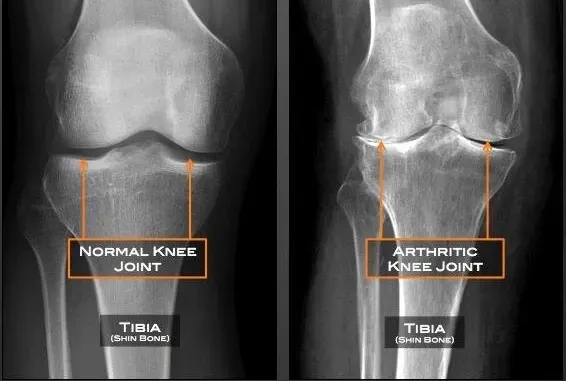

People with arthritis symptoms, such as swelling, stiffness, and pain in the joint

• Knee joint degeneration